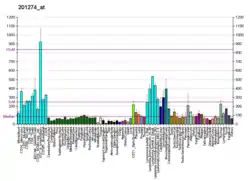

Gene expression levels of the proteasomal subunits (PSMA1, PSMA5, PSMB4, PSMB5 and PSMD1) were investigated in 80 patients with neuroendocrine pulmonary tumors and compared to controls. The study reviled that PSMB4 mRNA was significantly associated with proliferative activity of neuroendocrine pulmonary tumors.[34] However, a role of PSMA5 was also indicated in neuroendocrine pulmonary tumors. The PSMA5 protein has further been associated with the biosynthesis of conjugated linoleic acid (CLA) in mammary tissue.[35]